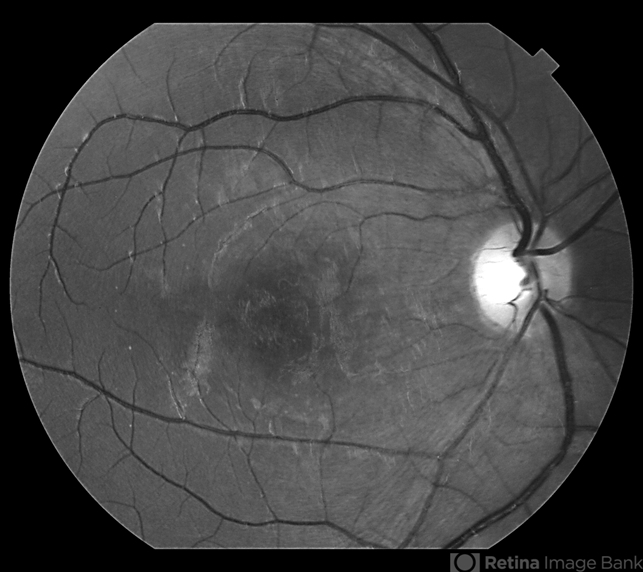

- diffuse unilateral subacute neuroretinitis (DUSN), larva, uveitis

Topcon TRC-50 Dx - Angulation of field photo of 35 Degrees, filter Red Free, flash 75 system 75, Digital Imaginet - Description

- Patient female, 15-year-old, he entered the clinic with complaint of low vision, visual acuity without correction was 20/60 in the right eye and 20/30 in the left eye. In the ocular exam of retinografia, there was change in the epithelium macular pigment and a small larva juxtafoveal above.